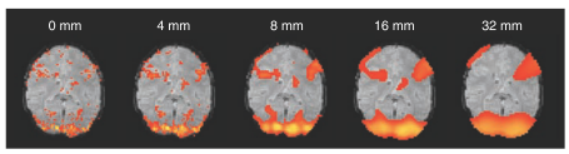

注:通常来说,平滑核的选取在不同的实验要求下有不同的标准,增加平滑核尺寸可导致检测到更大范围的激活区域,但会减弱对较小激活区域的检测能力,如下图 4所示。一般选取两倍于体素尺寸的平滑核,即若体素大小为3×3×3,一般选取FWHM=6mm。

图 4 平滑核尺寸对激活检测造成影响的例子